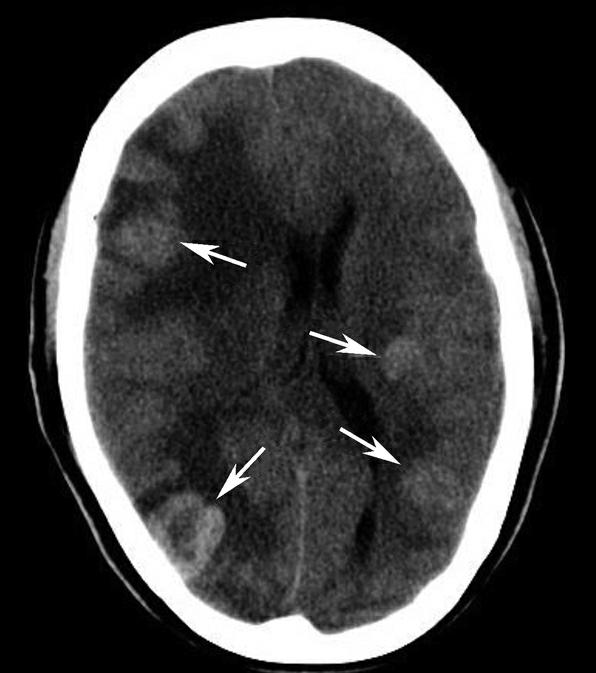

图1-2-87 脑挫裂伤并脑室内积血

右侧颞叶(白箭)、左侧基底节区(白箭头)大片状高、低混杂密度影。左侧侧脑室后角积血(黑箭)

图1-2-88 弥漫性轴索损伤

双侧额顶叶多发小片状高、低密度混杂影(箭)